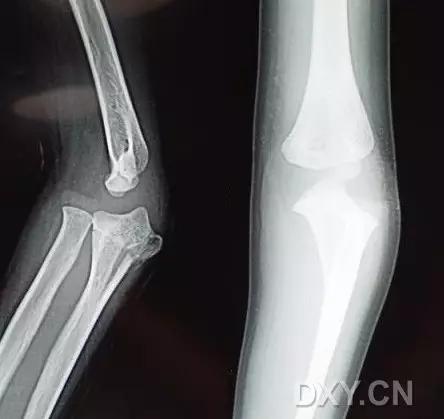

Hahn-steinthal 骨折 X 片(来源:Hahn-Steinthal fracture: a case report.BioMed central Cases Journal20081:239)

全肱骨小头骨折,为一种少见的关节内骨折,多见于成年人。常由于跌倒时手过度伸直或在屈肘时因桡骨小头撞击肱骨小头,并同时有外翻力存在时发病,亦可伴有滑车骨折与内侧副韧带的撕裂。X 线表现为全肱骨头骨折,向上移位。